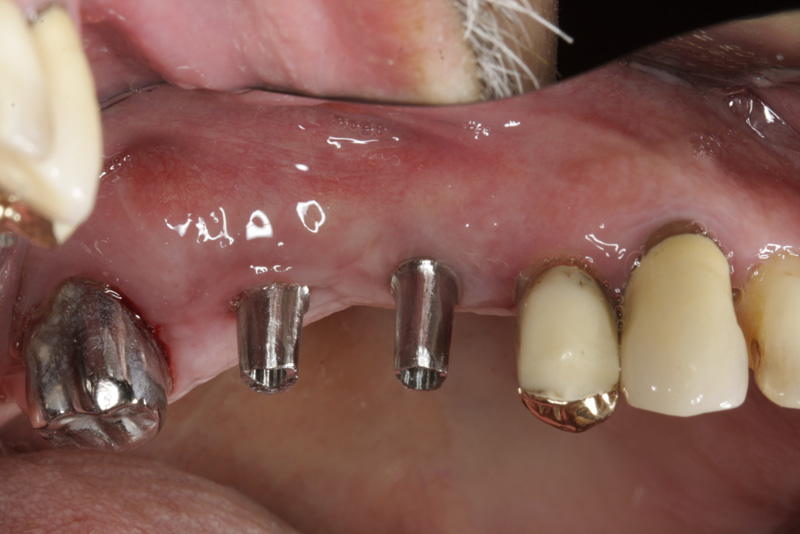

Během let může postupnou ztrátou zubů zůstat v ústech omezený počet zubů, které umožňují držení zubních náhrad.

V důsledku přetížení zbylých zubů např. houpavými pohyb snímacích náhrad dochází k uvolnění těchto zubů a držení můstků a protéz je tak velmi těžké. V těchto případech můžeme pomocí implantátů zvýšit počet pilířů a tím zabránit přetěžování a ztrátě zbylých zubů

S pomocí zubních implantátů můžeme díky různým kotevním systémům (třmeny, kulové hlavy, Locatory) zajistit stabilitu a držení protézy nebo při použití většího počtu implantátů zhotovit pevné náhrady – můstky nalepené nebo našroubované na pevno na implantáty.